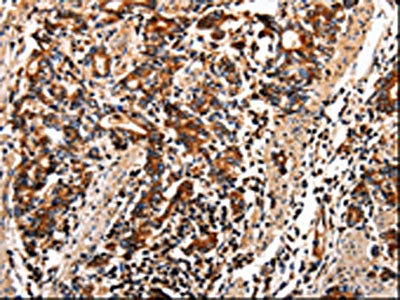

The image on the left is immunohistochemistry of paraffin-embedded Human stomach cancer tissue using CSB-PA143118(TTR Antibody) at dilution 1/10, on the right is treated with fusion protein. (Original magnification: ×200)